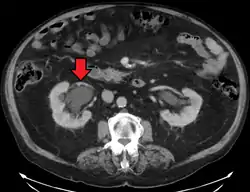

Hydronephrosis due to a kidney stone at the ureteral vesicular junction seen on CT scan

The choice of imaging depends on the clinical presentation (history, symptoms and examination findings). In the case of renal colic (one sided loin pain usually accompanied by a trace of blood in the urine) the initial investigation is usually a spiral or helical CT scan. This has the advantage of showing whether there is any obstruction of flow of urine causing hydronephrosis as well as demonstrating the function of the other kidney. Many stones are not visible on plain X-ray or IVU but 99% of stones are visible on CT and therefore CT is becoming a common choice of initial investigation. CT is not used however, when there is a reason to avoid radiation exposure, e.g. in pregnancy.